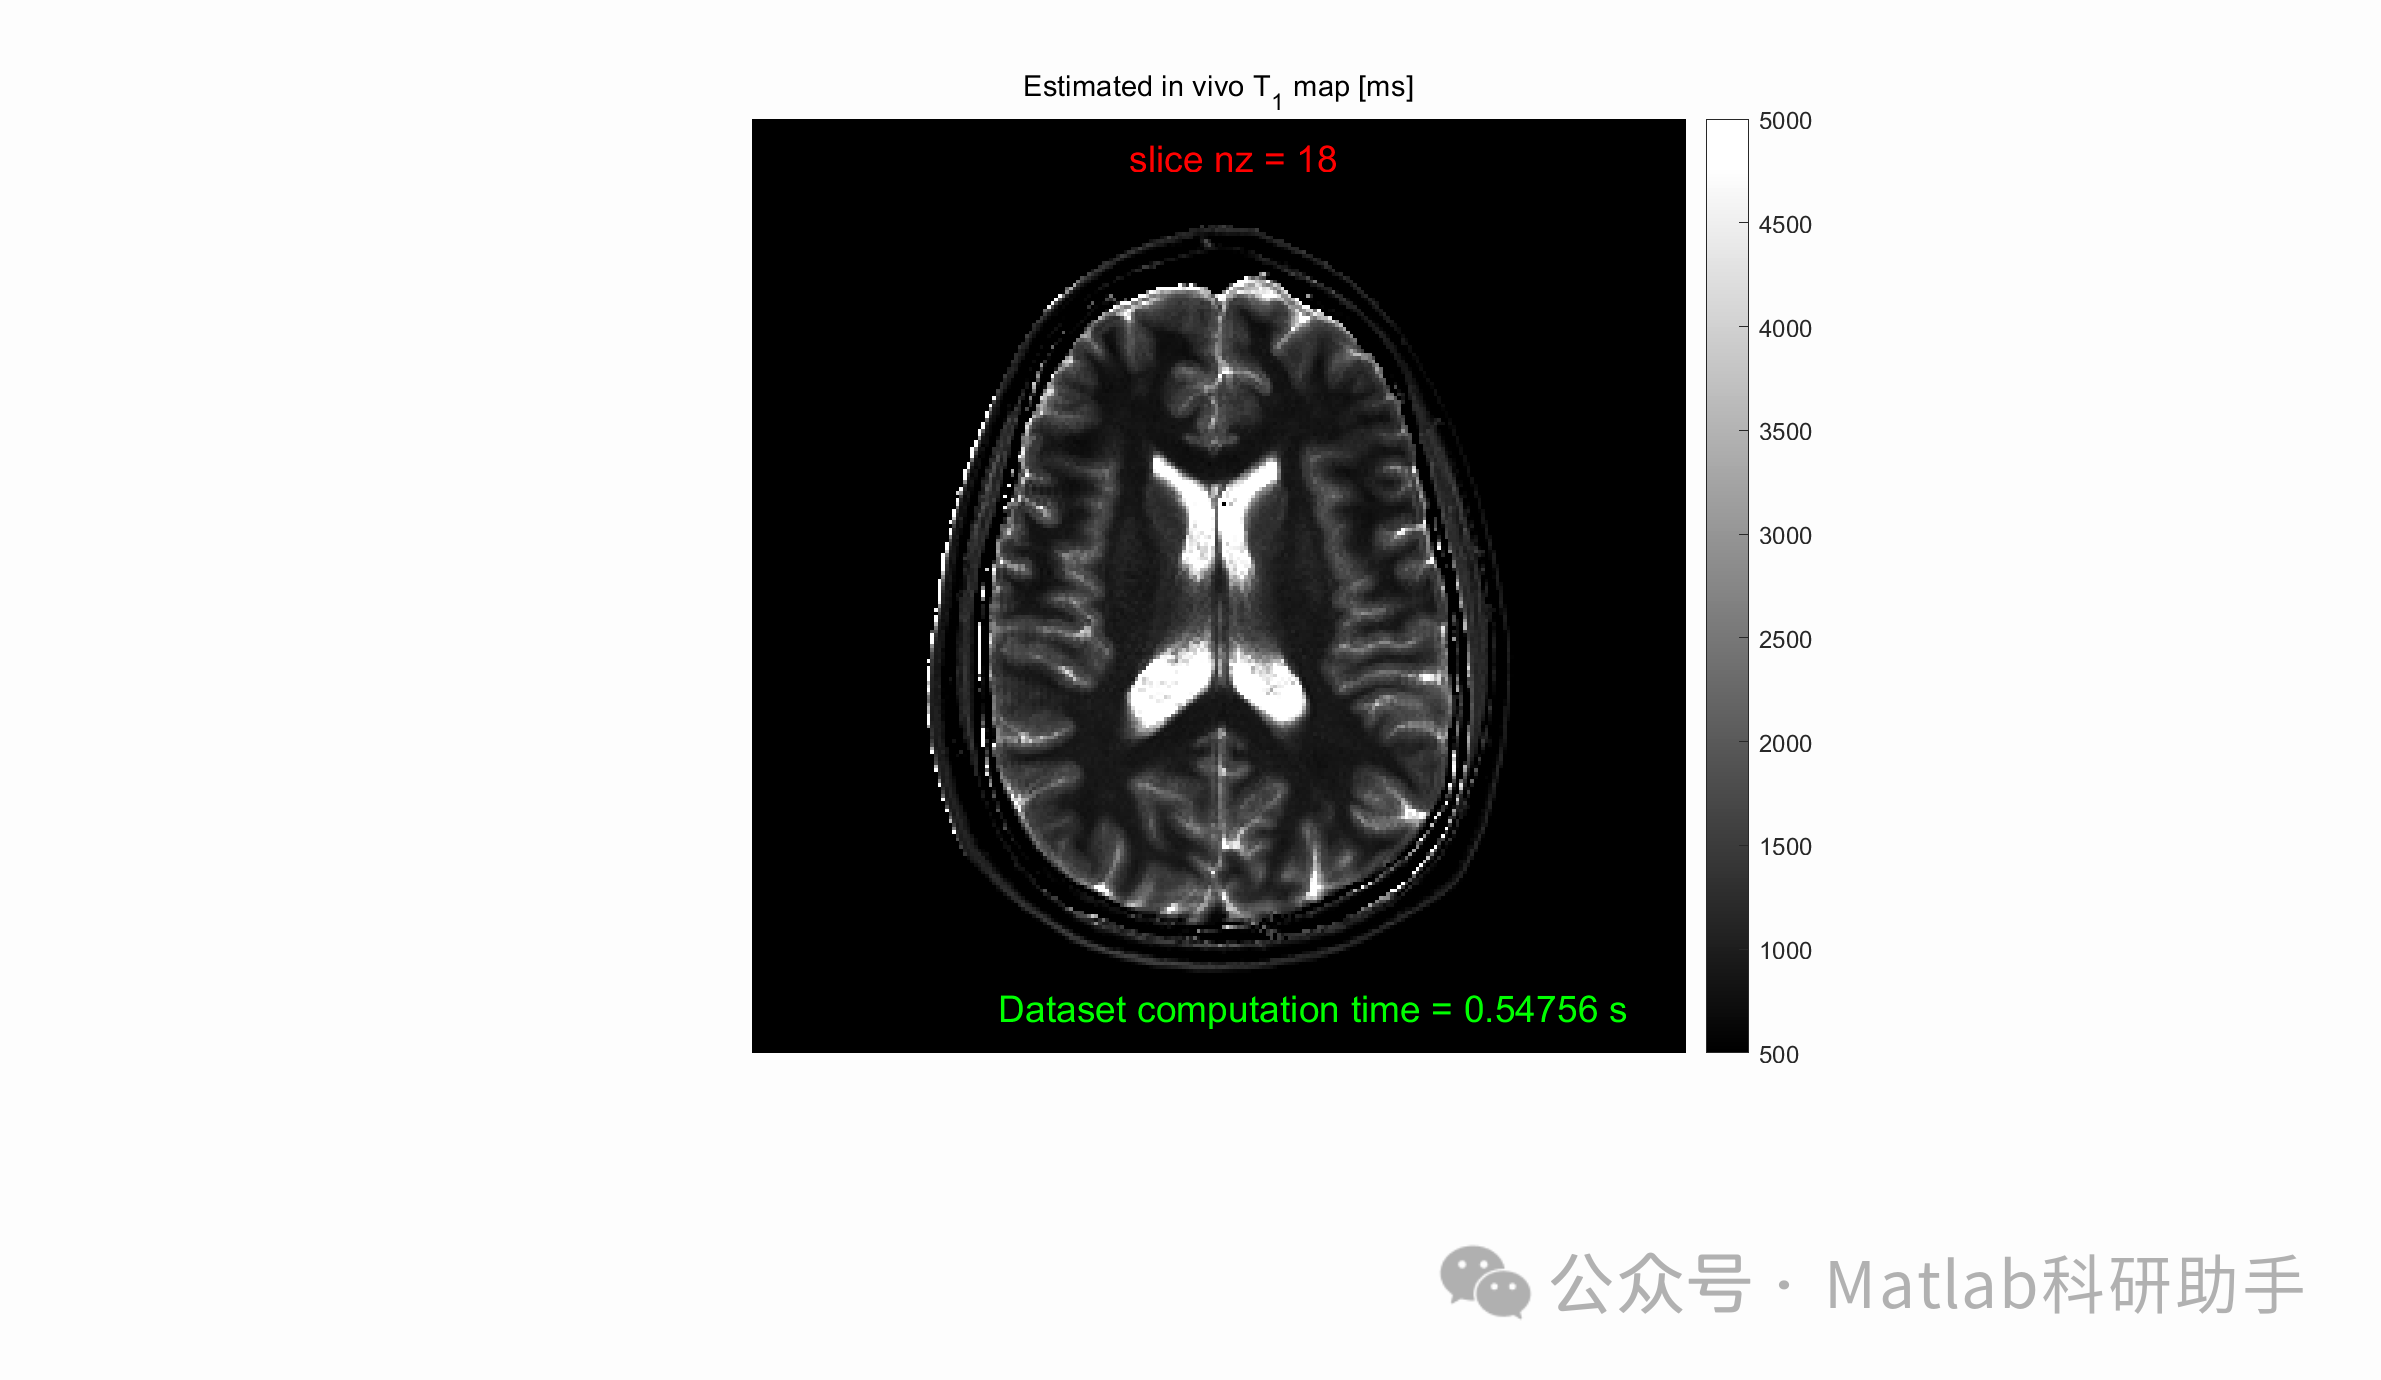

⛳️ 运行结果